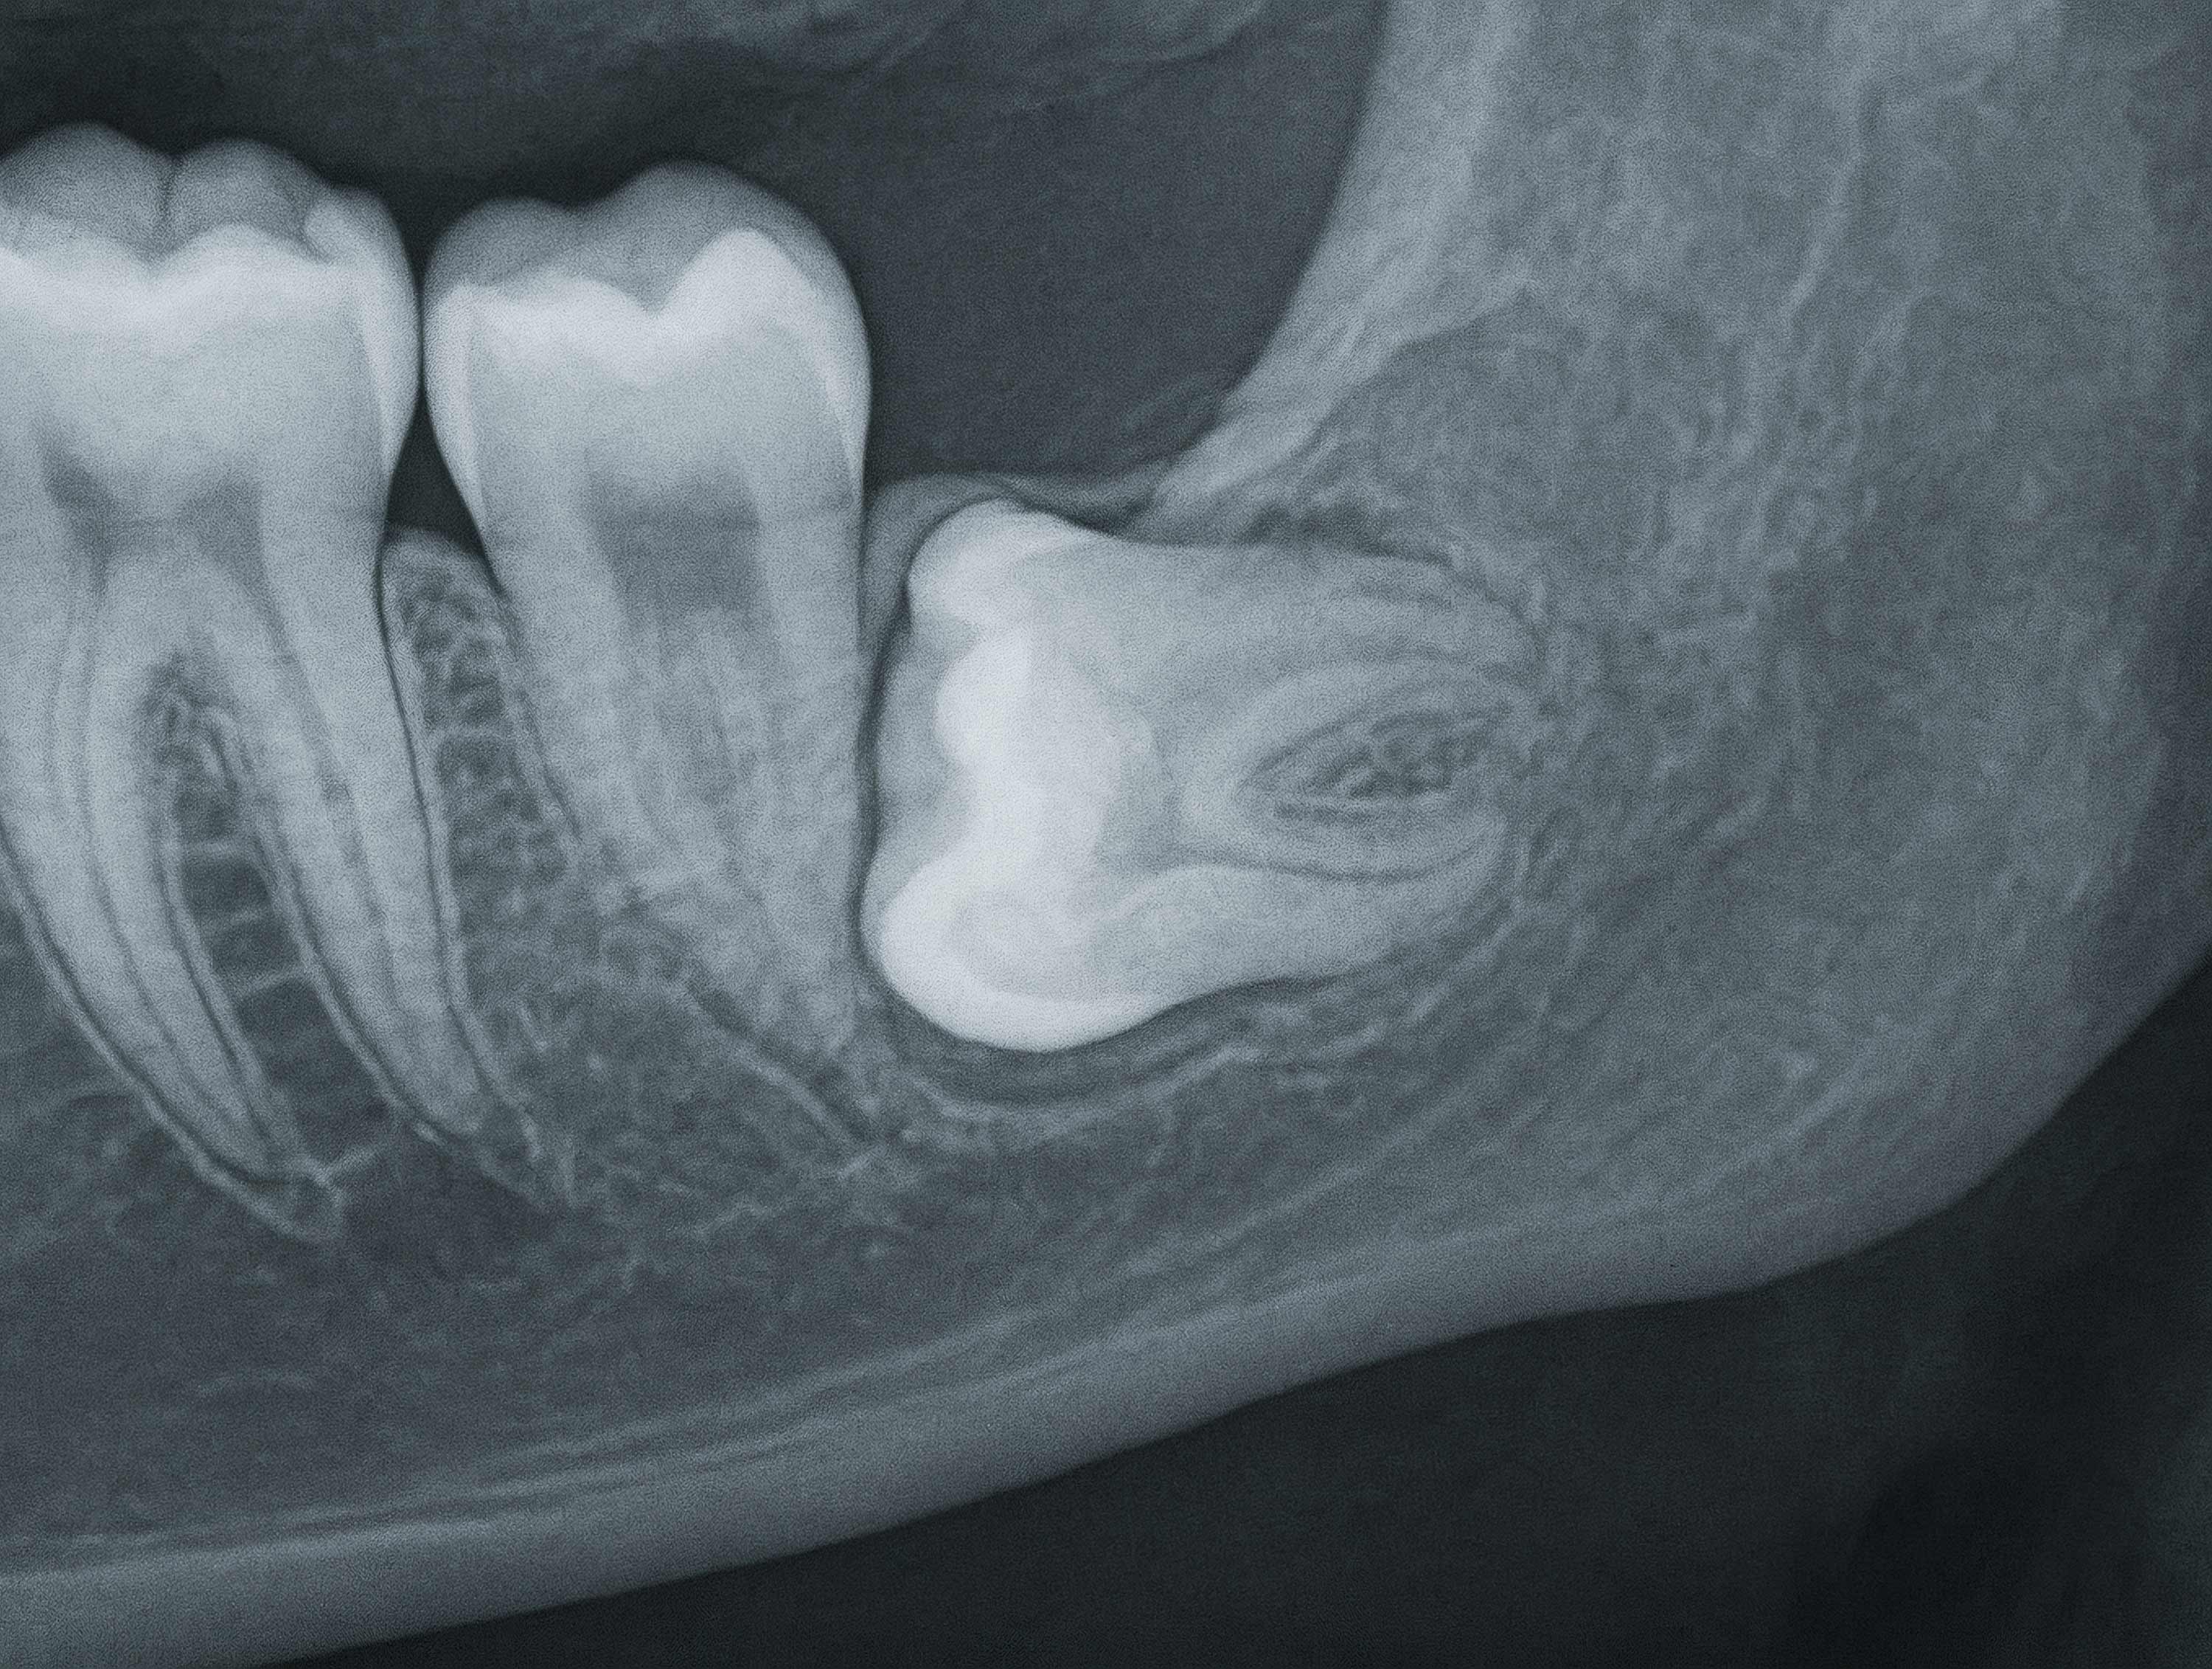

There are several reasons a patient may need a tooth removed—damage, infection, crowding, or impacted wisdom teeth. At Truro Dental Specialists, we focus on surgical extractions that require specialized care, often involving impacted teeth or roots below the gumline.

- Impacted third molars (wisdom teeth)

Wisdom teeth typically emerge in the late teens or early twenties, and often there isn’t enough space in the mouth to accommodate them. This can lead to:

- Development of cysts or damage to nearby teeth